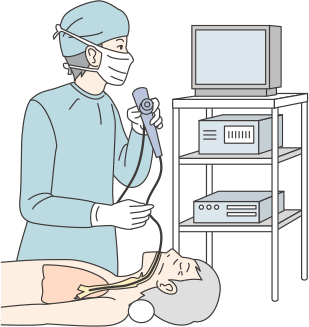

精密検査では、胸部CT検査や、気管支鏡検査などを行います。気管支鏡検査とは、口から気管支に内視鏡を入れて、がんができている可能性のある部位を直接観察する方法です。必要に応じて、その部位の細胞を採取して、悪性の腫瘍かどうかを診断します。

内視鏡検査

内視鏡検査は、口や鼻から気管支鏡を入れて行うものと、胸壁にあけた穴から胸腔鏡を入れて行うものがあります。気管支鏡検査は局所麻酔のみで、外来で行うことができる検査です。胸腔鏡検査は、全身麻酔が必要で患者さんへの負担も大きいため、気管支鏡検査で診断がつかないときに行われることがあります。

内視鏡検査:気管支鏡と胸腔鏡

気管支鏡とは

気管支鏡とは直径6mm程度のファイバーを鼻あるいは口から挿入し、先端のカメラで気管支の内部を観察したり、肺の組織を採取したりする検査です。かつては全身麻酔で水道管のような太いチューブを使っていましたが(硬性気管支鏡といいます)、日本の池田茂人氏によって気管支ファイバーが開発され、患者さんの負担が著しく軽減され、現在は局所麻酔で行われるようになりました。なお、硬性気管支鏡は検査の目的によっては今でも使われています。

気管支鏡を使った検査は、肺がんだけでなく、肺のさまざまな病気の検査としておこなわれています。気管支の粘膜や気管支がふさがっていないかどうかの観察、病巣の一部を採取、気管支内の異物除去、レーザー照射の治療にも用いられています。

ファイバーを挿入する口あるいは鼻に局所麻酔をかけた後、ファイバーをゆっくりと挿入し、気管や気管支内に局所麻酔液を散布しながら、ファイバーを気管支の奥に進めます。局所麻酔液を散布するのは、咳や異物感を軽くするためです。

気管支鏡検査は、気管支内部の観察だけであれば5分から10分で終了します。

病巣が直接確認できた場合、あるいはX線透視で病巣が確認された場合は、その部分の組織を擦過(擦り取ること)あるいは組織の一部を採取します。組織を採取しても痛みはありません。組織採取時の危険性としては出血があります。通常は10分程度で出血は収まりますが、稀に出血で入院等が必要となることも報告されています。

なお最近では、気管支鏡にカメラだけでなく超音波装置を備え(EBUS)、組織を採取する針のついた装置も開発されており、今までできなかった場所から検体が採取できるようになっています。

口あるいは鼻に局所麻酔を噴霧した後、ファイバーをゆっくりと挿入

気管支鏡の観察写真